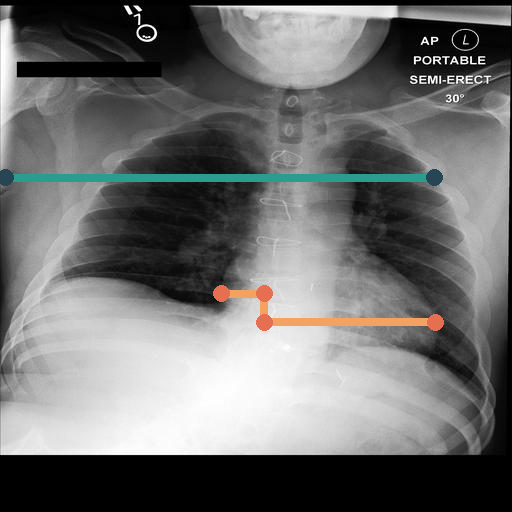

In Fig. 4, we show qualitative examples of the calculation of the cardio-thoracic-ratio for patients presenting cardiomegaly and not presenting cardiomegaly. For the case of the pathology, we see that the border of the heart is expanded, leading to a CTR above 0.7, whereas, for the absence case, the CTR is 0.4255.

When conducting a t-test, we get a value of 139.71 (p-value 0.0001) indicating a strong difference in CTR between positive and negative patients for cardiomegaly. We show this property in the violin plots on the left of Fig. 4, highlighting the CTR distributions for sex, age group, and pathology. Typically, the CTR for the presence and absence of cardiomegaly has noticeable shifts, with both respective means increasing with age. This average increase in CTR, however, becomes less in the age group of , with the disparity in mean CTR between cardiomegaly and no cardiomegaly reducing the older a patient gets. This result, in turn, lessens the insight of CTR with age. We observe this property for male and female patients. On the right of Fig. 4, we show the ROC-Curve for pathology classification based on the CTR score. We see a difference in the diagnostic performance of the CTR for female and male patients with an AuROC of 0.73 and 0.75.